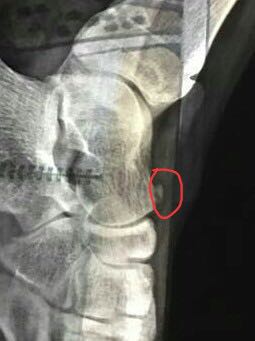

查体:左足踝及足部软组织略肿胀,中后足背侧体表可见突起肿物,质硬,无移动度,触压痛阳性,叩击Tinel征阳性,足位于跖屈内翻位时,症状加重(这一活动可使腓浅神经张力增高,更易激惹)。 辅查:足部侧位片可见距骨上缘外生骨疣(刺激腓浅神经)。

诊断:腓浅神经卡压综合征(占位性病变) 治疗:考虑在局部麻醉下行外生骨疣病灶清除,去除神经卡压治病因素。